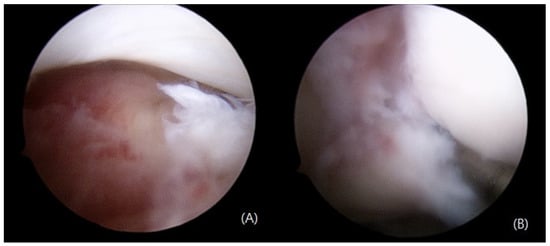

2. Case Presentation